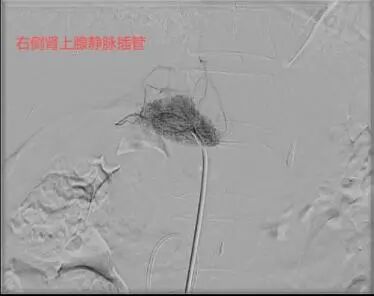

导管“寻路”:医生在X光引导下,通过血管造影精准导航,将导管送至肾上腺静脉,过程约30分钟。

采血化验:左右两侧各取3-5毫升血(约一茶匙),检测醛固酮和皮质醇水平。

58岁的杨先生患高血压多年,平日里血压控制不佳,近1年来出现血钾减低,间断进行补钾治疗后仍无法将血钾维持在正常范围。于是来到市四医院寻找原因,CT提示左侧肾上腺结节样增生,考虑杨先生存在原发性醛固酮增多症,为了明确双侧肾上腺的优势分泌侧来准确指导外科手术方案。医院介入室团队为患者进行了双侧肾上腺静脉采血术,血检结果提示左侧肾上腺为优势分泌侧。2周后,杨先生在泌尿外科接受了腹腔镜下左侧肾上腺切除术,术后血压恢复正常,无需药物辅助控制。